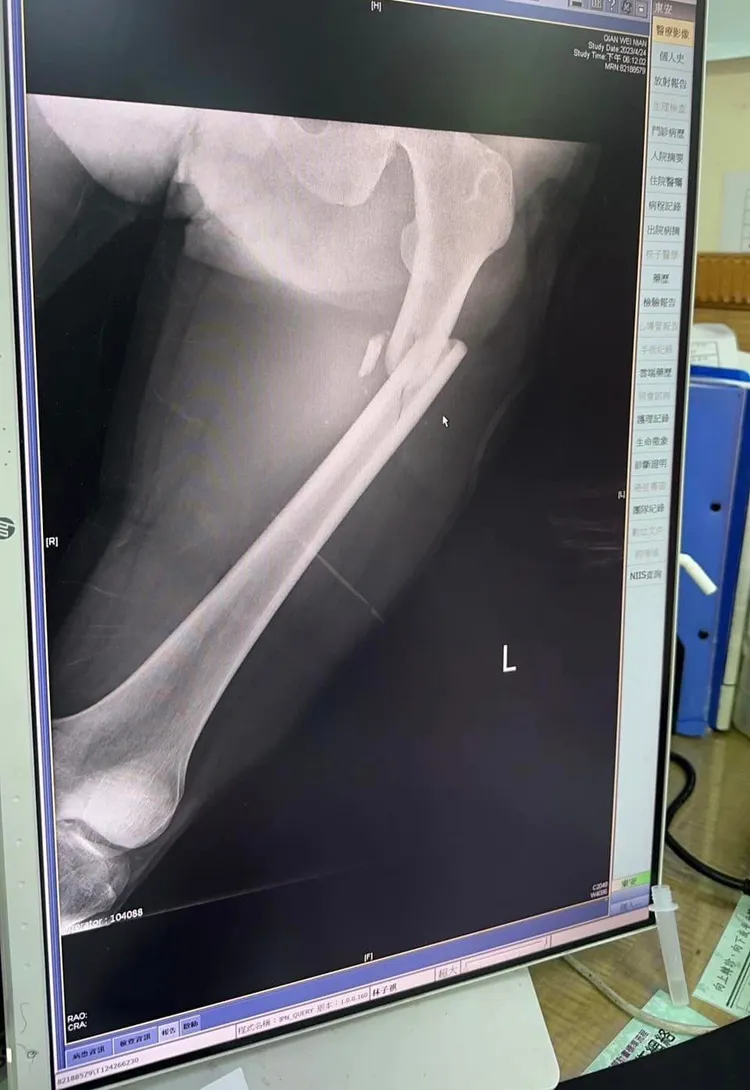

她表示,親弟弟騎機車直行,遭酒駕汽車對撞,弟弟雙腿開放性,粉碎性骨折,骨盆裂了,質疑是不是要等到大法官,還是執法人員的家人身上,才會感同深受?法令才會修改嚴懲?「我真的不知道要罵什麼了,真的…」。